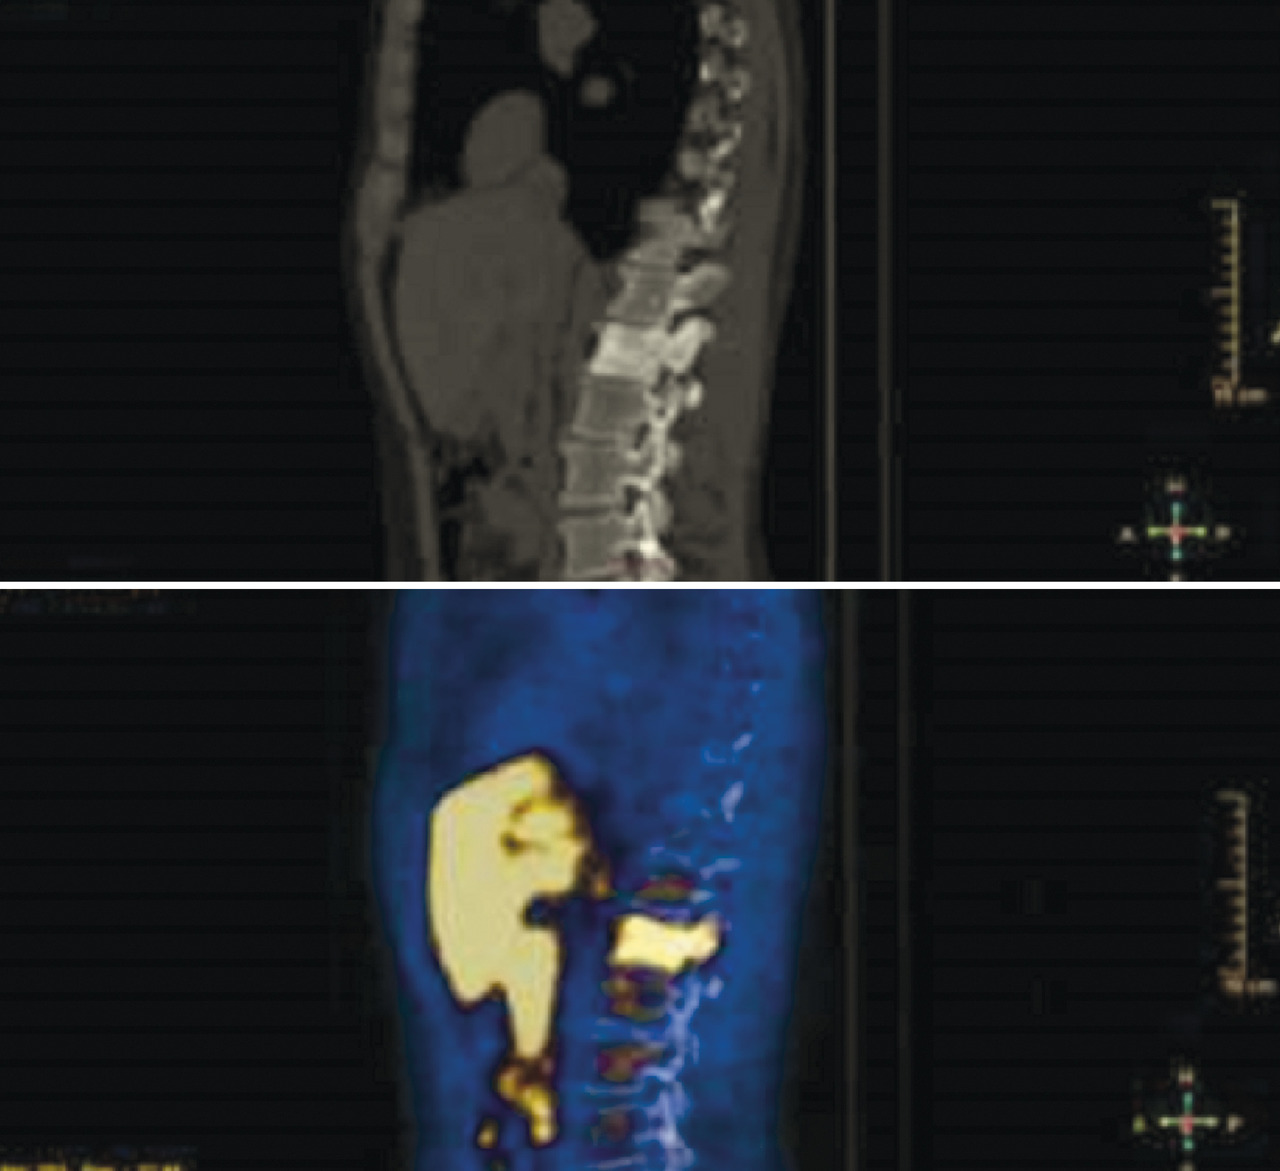

Plus récemment, d’autres méthodes d’imagerie ont permis d’améliorer la précision du bilan d’extension, notamment la tomographie par émission de positons (TEP), avec différents traceurs. La TEP est un examen d’imagerie fonctionnelle qui permet de mesurer en trois dimensions l’activité métabolique des tissus. Elle est couplée à un scanner classique, qui permet de préciser les zones d’hypermétabolisme par superposition des deux iconographies. La TEP repose sur le principe général de la scintigraphie, qui consiste à obtenir des images après l’injection d’un « traceur » faiblement radioactif : pour l’étude des cancers de prostate, le plus largement utilisé est le [18F]fluorocholine (fig. 3). Ce traceur va se fixer sur les tissus cibles qui vont émettre, de façon temporaire, une radioactivité que l’on peut suivre dans l’organisme du patient et qui peut offrir des informations importantes surtout dans l’évaluation des ganglions locorégionaux et de l’extension à distance de la maladie. Cependant, il existe encore des controverses sur l’utilisation correcte de ces méthodes.